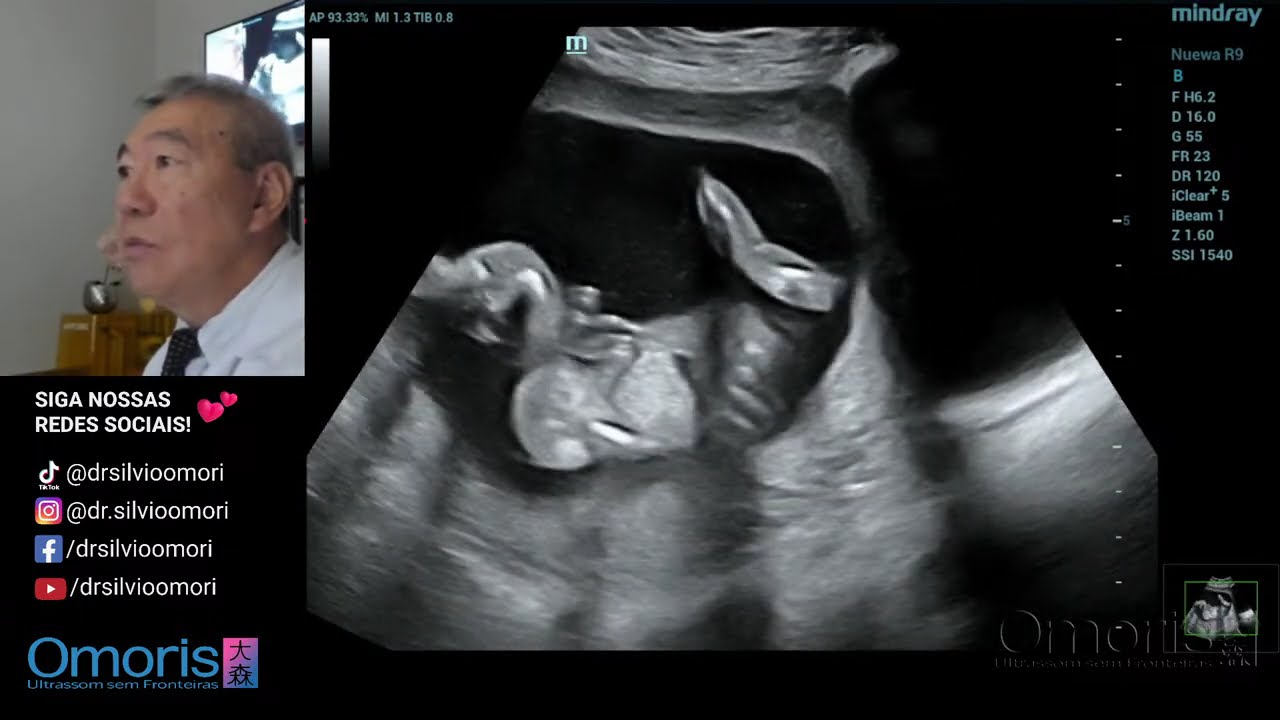

Sexagem GEMEOS 15 semanas

Автор: Dr. Silvio Omori

Dr. Silvio Takao Omori CRM-PR 8227 RQE 27208

#gravidez #gestante #ultrassom #gestacao #sexagemfetalrimeiro B